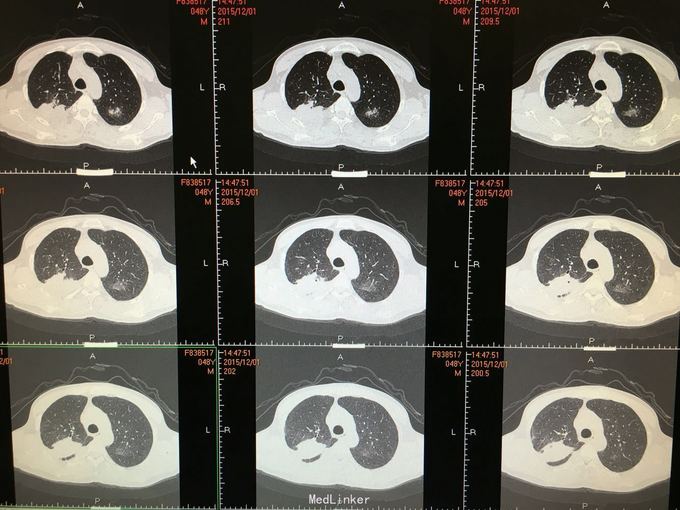

间断咳嗽咳痰5月余。患者缘于半年前确诊为骨髓增生异常综合征,并行造血干细胞移植术。术后出现发热,完善相关检查考虑为肺部真菌感染,给予抗感染治疗后体温正常,病情好转出院。出院后仍有间断咳嗽咳痰,咳黄色痰,无发热,自行口服伏立康唑200mg,2/日治疗,12月初复查CT提示双肺病灶较前进展,右肺中叶新增病灶。

根据症状体征及辅助检查,结合病史考虑真菌感染可能性大。进一步气管镜检查,结果如下。组织活检标本可见。病理回报提示真菌团,培养见曲霉菌生长。明确诊断后给予两性霉素B雾化吸入及伏立康唑静脉应用抗真菌治疗,同时给予环孢素口服。

造血干细胞移植后肺部感染常见,其中以曲霉、卡肺等多见,患者经气管镜检查已将真菌团块取出。术后给予监护,口服云南白药、垂体后叶素雾化止血等治疗,无明显出血,症状逐渐好转。复查CT也明显好转。